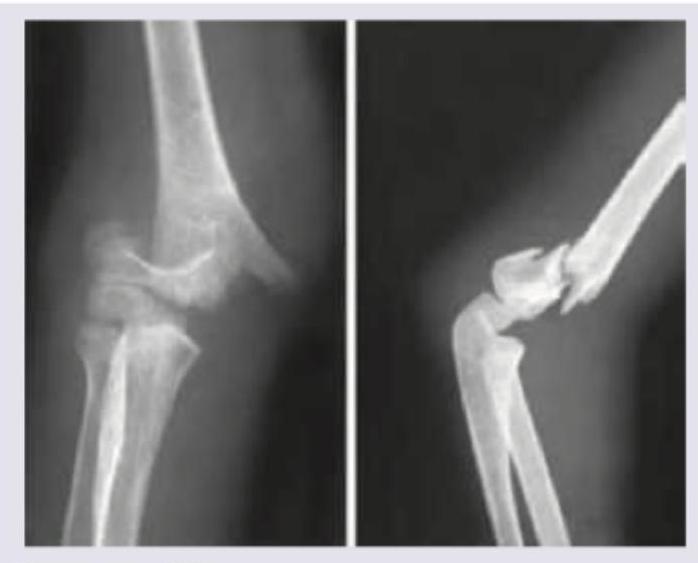

A 7-year-old child presents to the emergency department after a fall on an outstretched hand. The following X-ray of the elbow shows:

Explanation: ***Supracondylar fracture humerus*** - The image displays a clear **fracture of the distal humerus**, specifically above the condyles, with significant displacement of the distal fragment. - This type of fracture commonly occurs in children due to a fall on an outstretched hand and carries a risk of neurovascular compromise due to its proximity to vital structures like the **brachial artery** and **median nerve**. *Fracture tibia* - The image shows bones of the arm, specifically around the elbow joint, not the lower leg. - Fractures of the tibia would appear in an X-ray of the lower leg, typically involving the shaft or ends of the **shin bone**. *Fracture radius* - While the **radius** is visible in the image as one of the forearm bones, the primary fracture site is clearly in the **humerus** above the elbow joint, not the radius itself. - A radial fracture would involve the bone on the thumb side of the forearm. *Colles fracture* - A **Colles fracture** is a specific type of fracture of the **distal radius**, characterized by dorsal displacement of the distal fragment and typically occurs near the wrist joint. - The image clearly depicts a fracture localized to the **elbow region**, not the wrist, and involves the humerus.